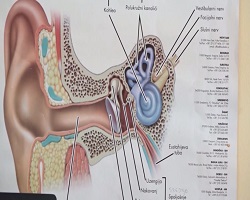

Током лета се дешава да због незгодног скока у воду дође до пуцања бубне опне. Начелник Одељења за ухо, грло, нос доктор Вељко Божић наглашава да се треба јавити лекару и да је погрешно лечити се на своју руку, јер то може довести до оштећења слуха и операције која би могла да се избегне уколико се дође код лекара одмах после повређивања. |